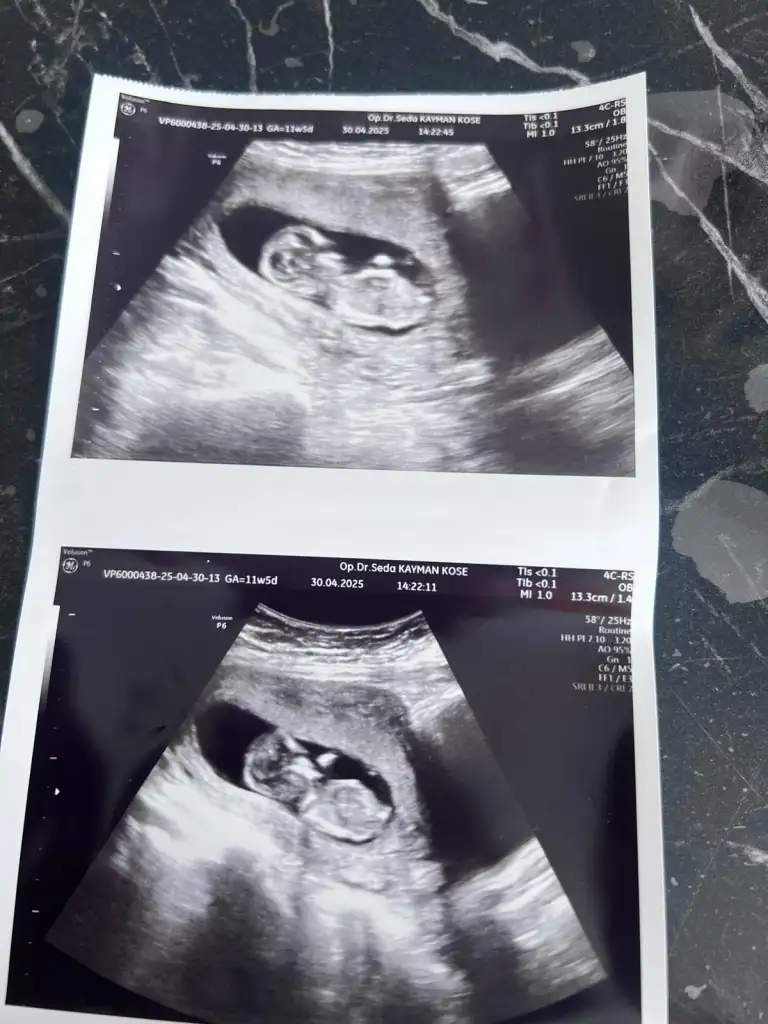

Banada bakar mısınız 12 haftalık

• 772a7cb7-dd46-4148-b878-492734ef6f59.webp

39,1 KB · Görüntüleme: 50

• 0ae49c84-b353-4504-ba74-de5b3a1e9d6a.webp

48,1 KB · Görüntüleme: 51